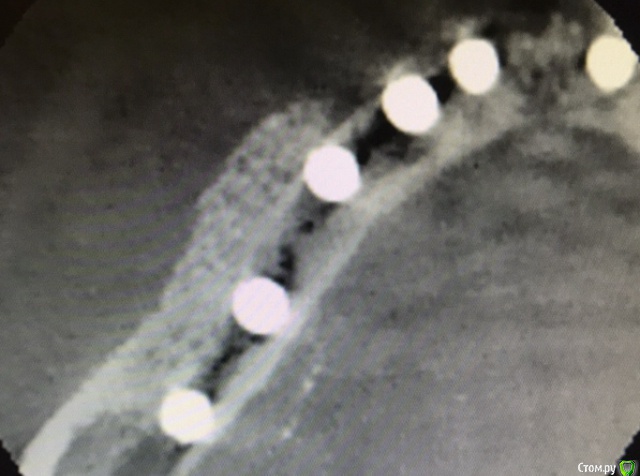

колесников Опубликовано 29 сентября, 2019 Автор Поделиться Опубликовано 29 сентября, 2019 (изменено) Старая чужая работа в плане хирургии и свежая ортопедия ,пациентка мнительная и знакомая учередителей и хирург и ортопед их старые знакомые и ещё цементная фиксация. Нужно было сделать минимально инвазивно,без переделки коронок,без периода «без зубов» и сильно не умничать. Были жалобы на застревание пищи ,на тянущие ощущения и прочий дискомфорт. Десна выглядела тонкой,просвечивались абатменты,но к счастью без воспаления,это фрезерованные Нобеля. У шеек десна так и осталась тонкой ,но ушло напряжение. По снимку я показал какой был гребень и какой стал валик,валик ниже вершины гребня,ниже шеек имплантов. Отслаивать тоннельно при стоящих имплантат в верх-очень рисковано ,можно потерять герметизм и все стухнет. Потому,пусть тонка но прикреплённая слизистая остаётся там где она есть,амниже располагается костный валик,теперь нет напряжения в мягких тканях на вершине гребня,они будут постепенно созревать под воздействием ирригатора. Обычно после я делаю стрип пластику,но врядли мне это дадут сделать. Фото через неделю сделаю Вот вчера подобное делал. Тоже Нобеля и тоже снимать нельзя ,осложнено положением имплантов в 45градусов и импланты на 1/3 Вестибулярно не в кости. На выглядит более менее,но это все мягкие ткани Изменено 29 сентября, 2019 пользователем колесников Ссылка на комментарий

Большой Зеленый Опубликовано 25 июня, 2020 Поделиться Опубликовано 25 июня, 2020 Улучшение объема и качества мягких тканей в пришеечной области у ранее поставленных имплантов ,посредством тоннельной костной пластики. Объём 0,5г. Вид через 6 мес.Срезы на разном уровне. Не объективная картинка Ссылка на комментарий

колесников Опубликовано 25 июня, 2020 Автор Поделиться Опубликовано 25 июня, 2020 Подтянуть первую ко второй или вторую к первой?). Аугментат созрел и интегрирован-в этом суть контрольного снимка,снимок «до» даёт понимание по объёму и форме дефекта. Вот так выглядит свежий графт (1),вот так созревший (2). И поперечные срезы. Все это уже давно запротезировано. Ссылка на комментарий